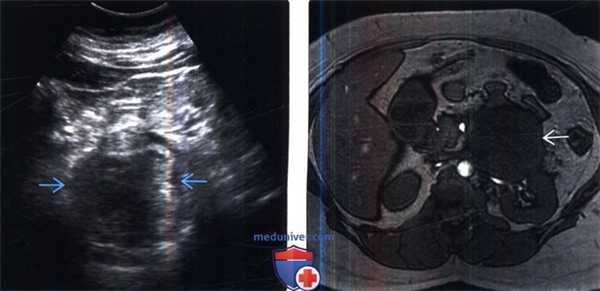

(Слева) УЗИ в поперечной плоскости: у пациента с отсутствием симптомов в левом верхнем квадранте выявлено дольчатое мягкотканное образование.

(Справа) МРТ, противофазное Т1-ВИ, аксиальная проекция: у этого же пациента визуализируется мягкотканное образование со средней мягкотканной ИС. По сравнению с синфазной последовательностью (не показано) при противофазной последовательности не было потери сигнала. При резекции интраоперационная картина соответствовала злокачественной фиброзной гистиоцитоме.